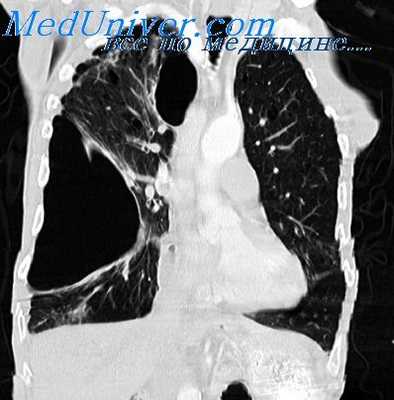

- Компьютерная томография. КТ ОГК производится для уточнения характера повреждений, выявления ателектазов, пневмо- и гемоторакса, других патологий, выполняется нативно или с контрастом. Пациентам также могут быть показаны КТ легких или КТ средостения. Для детализации изменений, обнаруженных на рентгенограммах костей лица, могут быть назначены КТ орбиты и другие исследования.

Диагностика буллезной эмфиземы легких основывается на клинических, функциональных и рентгенологических данных. Курация больного осуществляется пульмонологом, а при развитии осложнений – торакальным хирургом. Рентгенография легких не всегда эффективна в выявлении буллезной эмфиземы легких. В то же время, возможности лучевой диагностики существенно расширяет внедрение в практику КТ высокого разрешения. На томограммах буллы определяются как тонкостенные полости с четкими и ровными контурами. При сомнительном диагнозе удостовериться в наличии булл позволяет диагностическая торакоскопия.